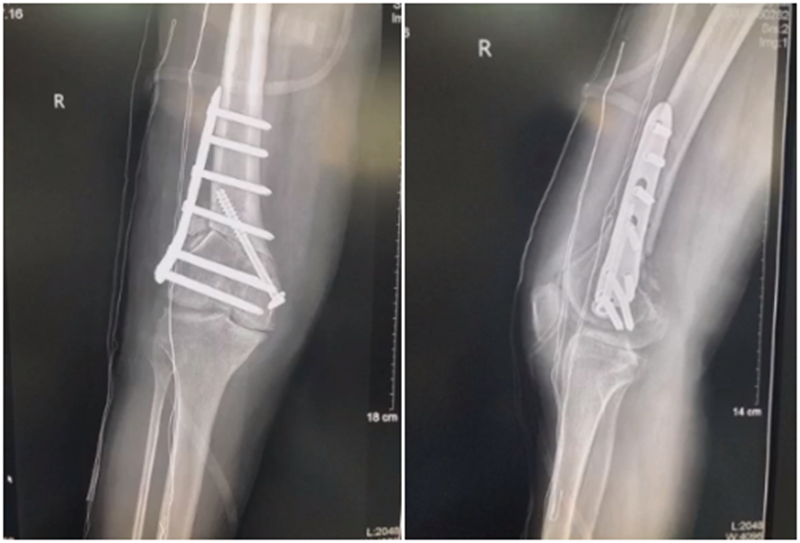

(1)合页骨折

对于术中出现的合页骨折,此时还有一定的稳定性,可以调整力线固定以后,由前外向后内打一根防旋螺钉,这样仍然是比较稳定,术后康复计划与正常一样。

对于术中合页骨折,但非常不稳定、无法控制力线的情况,可以由外侧向股骨外髁打入一枚2.0的克氏针,因为克氏针具有一定弹性,相当于重建合页临时稳定性,在此基础上再去调整力线,做固定。

术后做植骨,早活动、晚负重,避免做扭转活动。

晚期出现的合页骨折,此时力线已经改变,只能进行翻修。

(2)术后力线丢失

对于力线丢失原则是重新矫正力线,重新固定,通常在合页端加上内固定物,主要目的是为了抗旋,有一些截骨端还需要进行植骨。术后早活动晚负重。